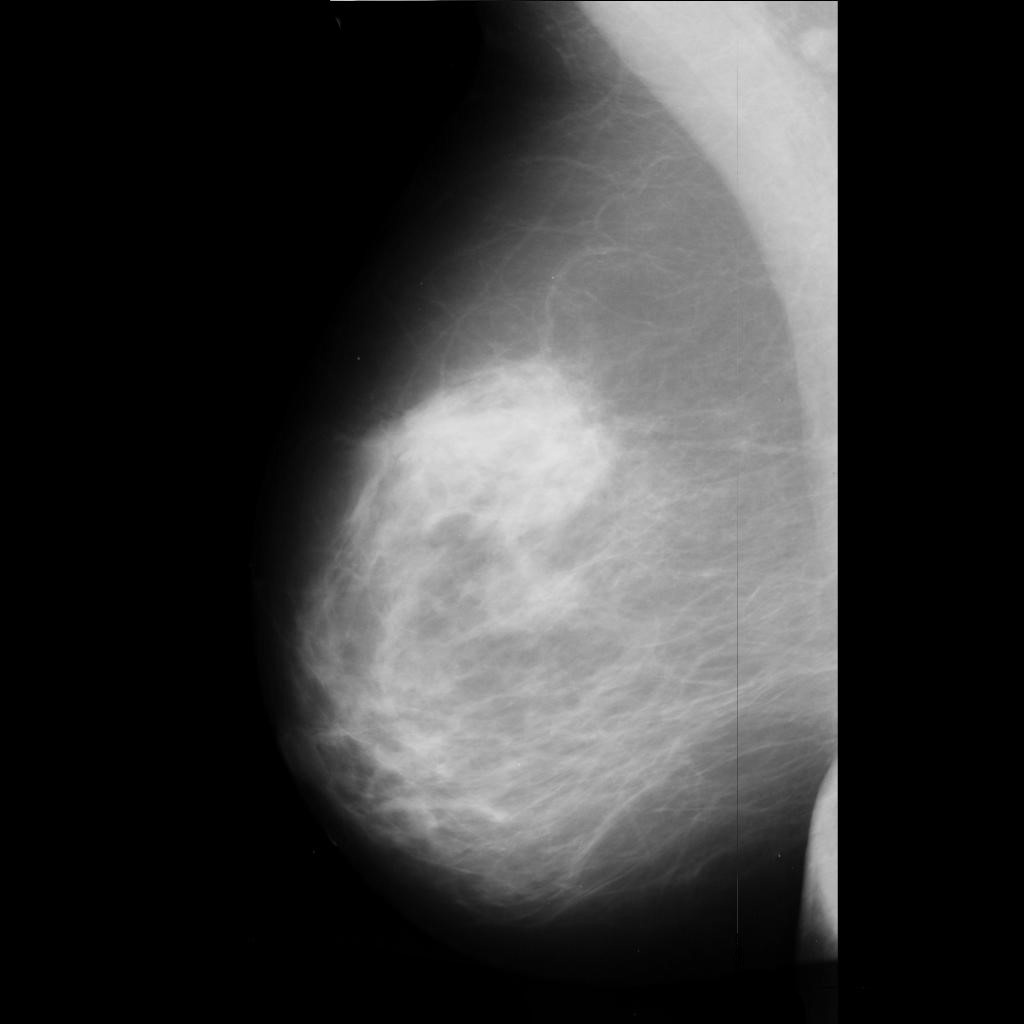

benign